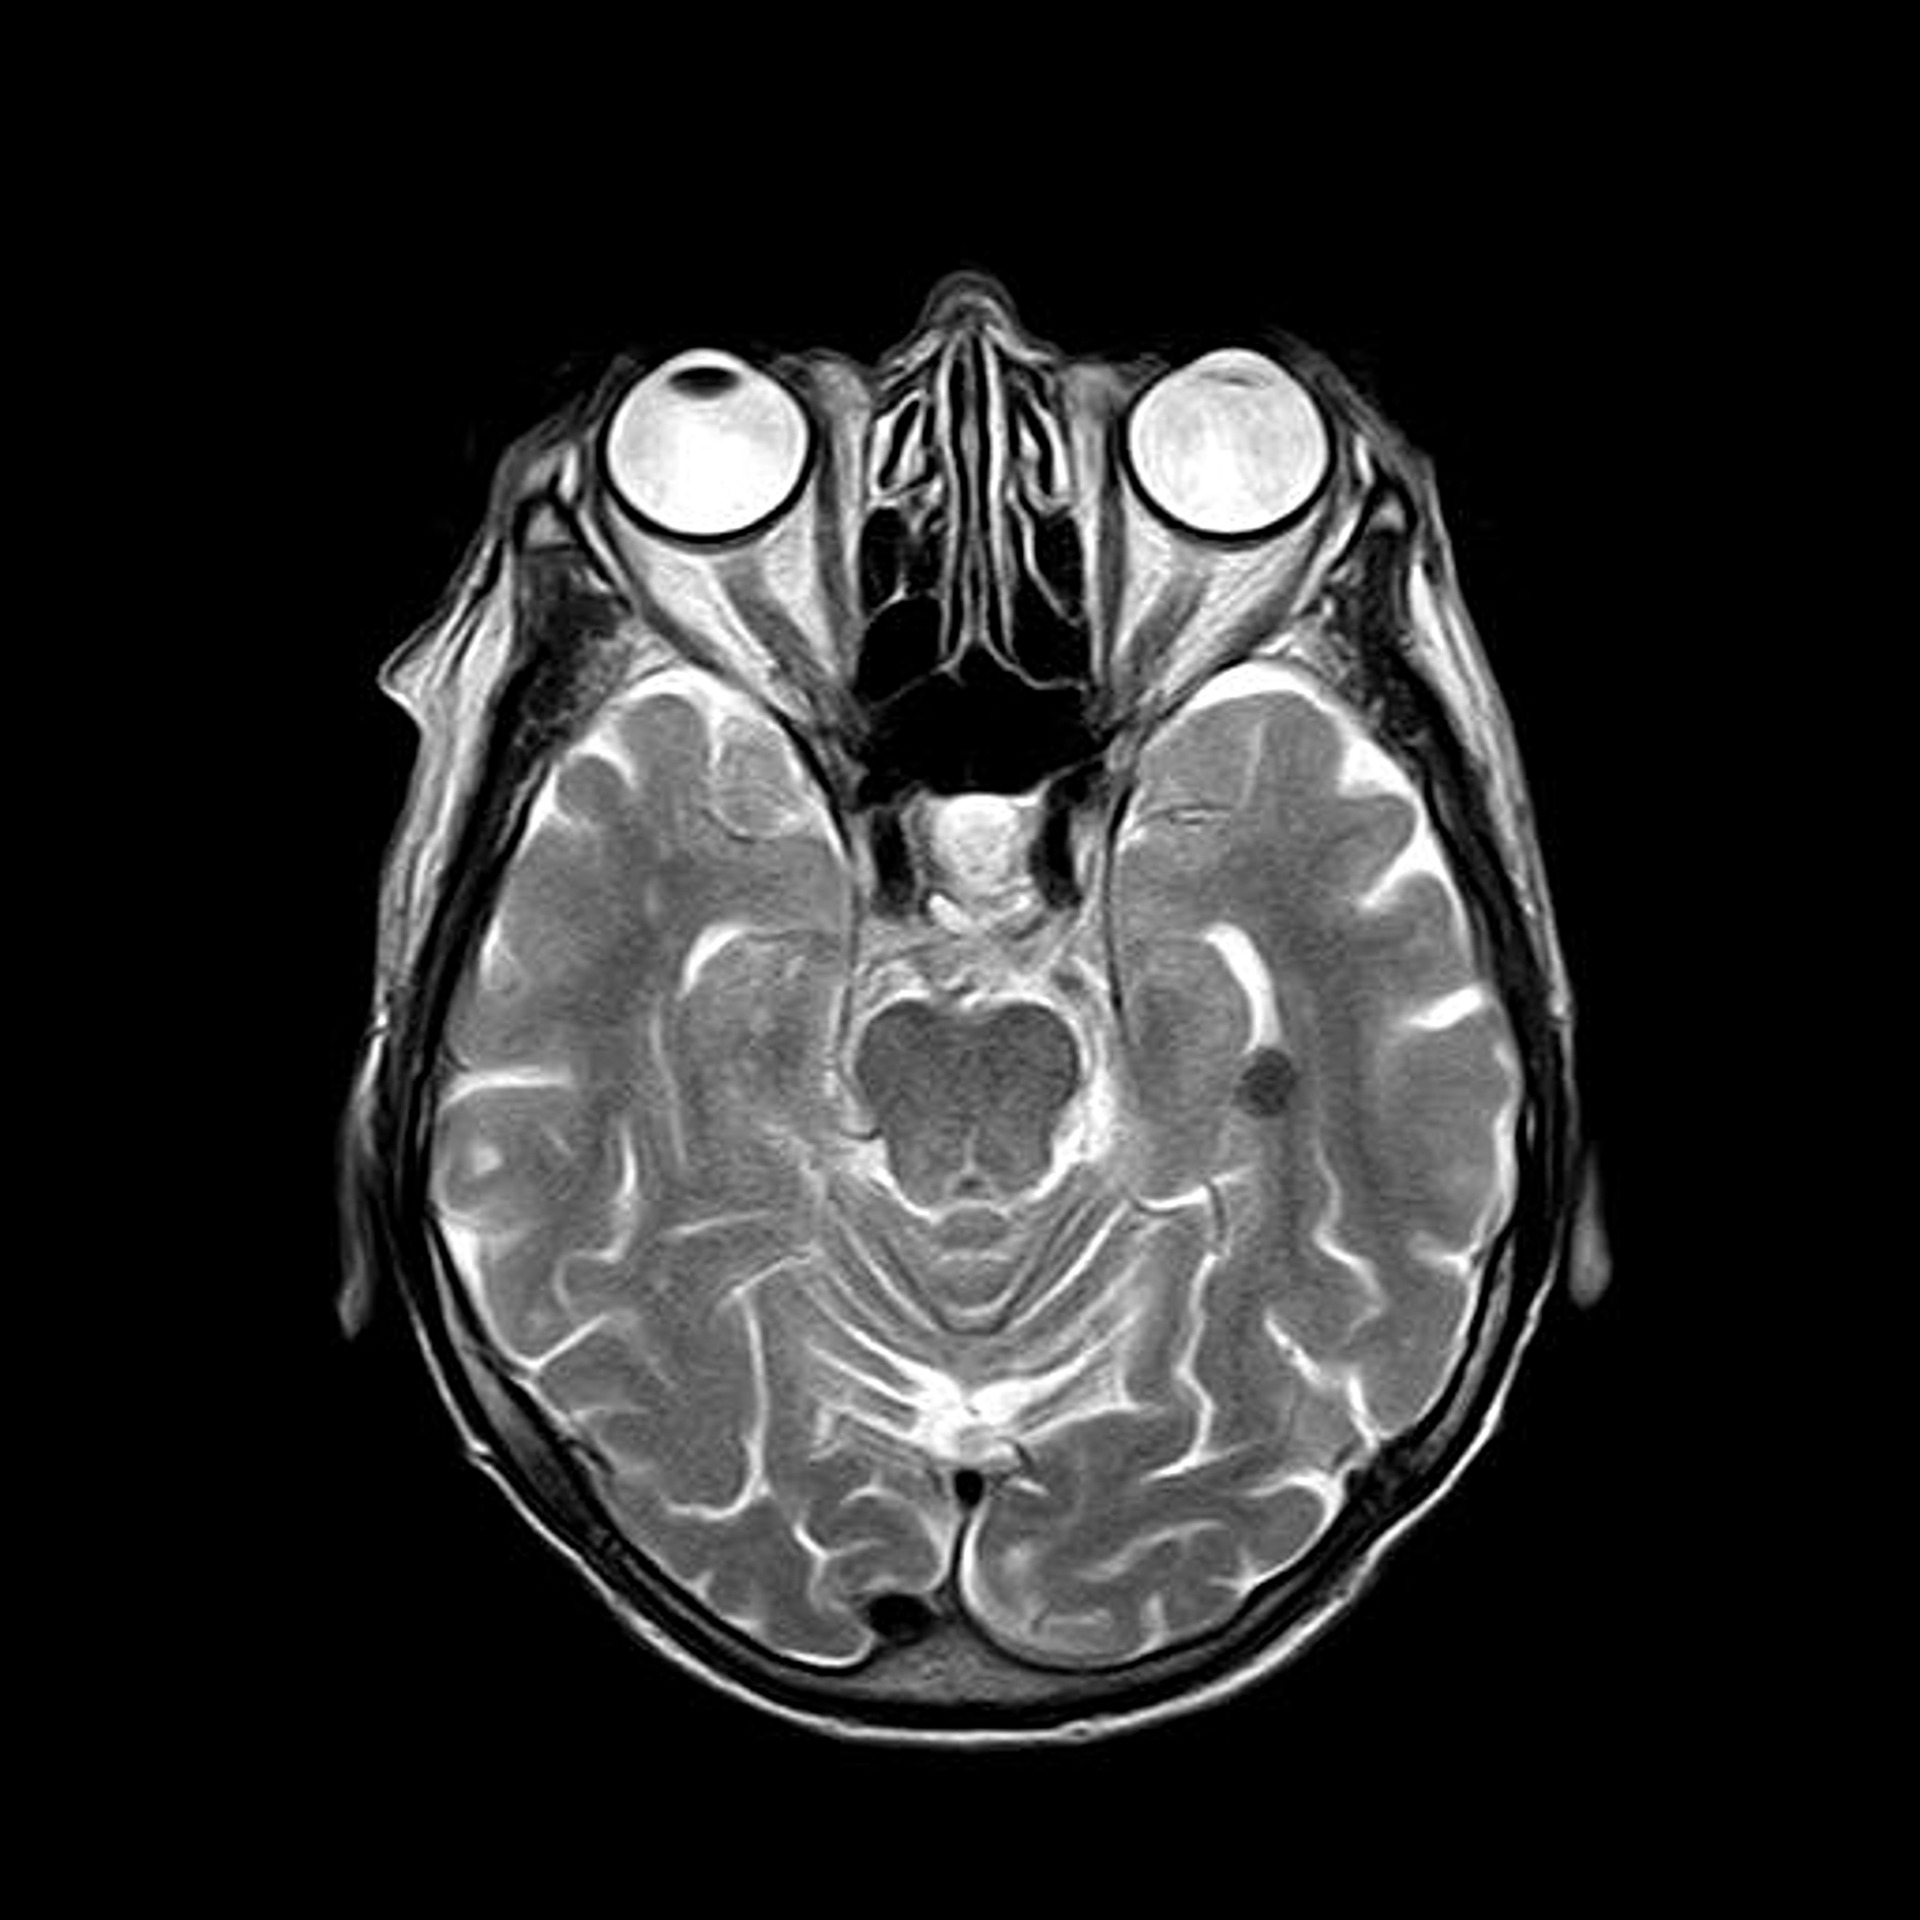

La tecnica è una forma modificata di stimolazione magnetica transcranica (rTMS) e funziona erogando alte dosi di impulsi magnetici nel cervello di un paziente con un dispositivo contenente bobine magnetiche posizionate all’esterno del cranio.

Il trattamento richiede solo cinque giorni ed è personalizzato per ogni paziente sulla base di una scansione MRI che riduce la tempistica tipica del trattamento rTMS da un arco di settimane a pochi giorni.